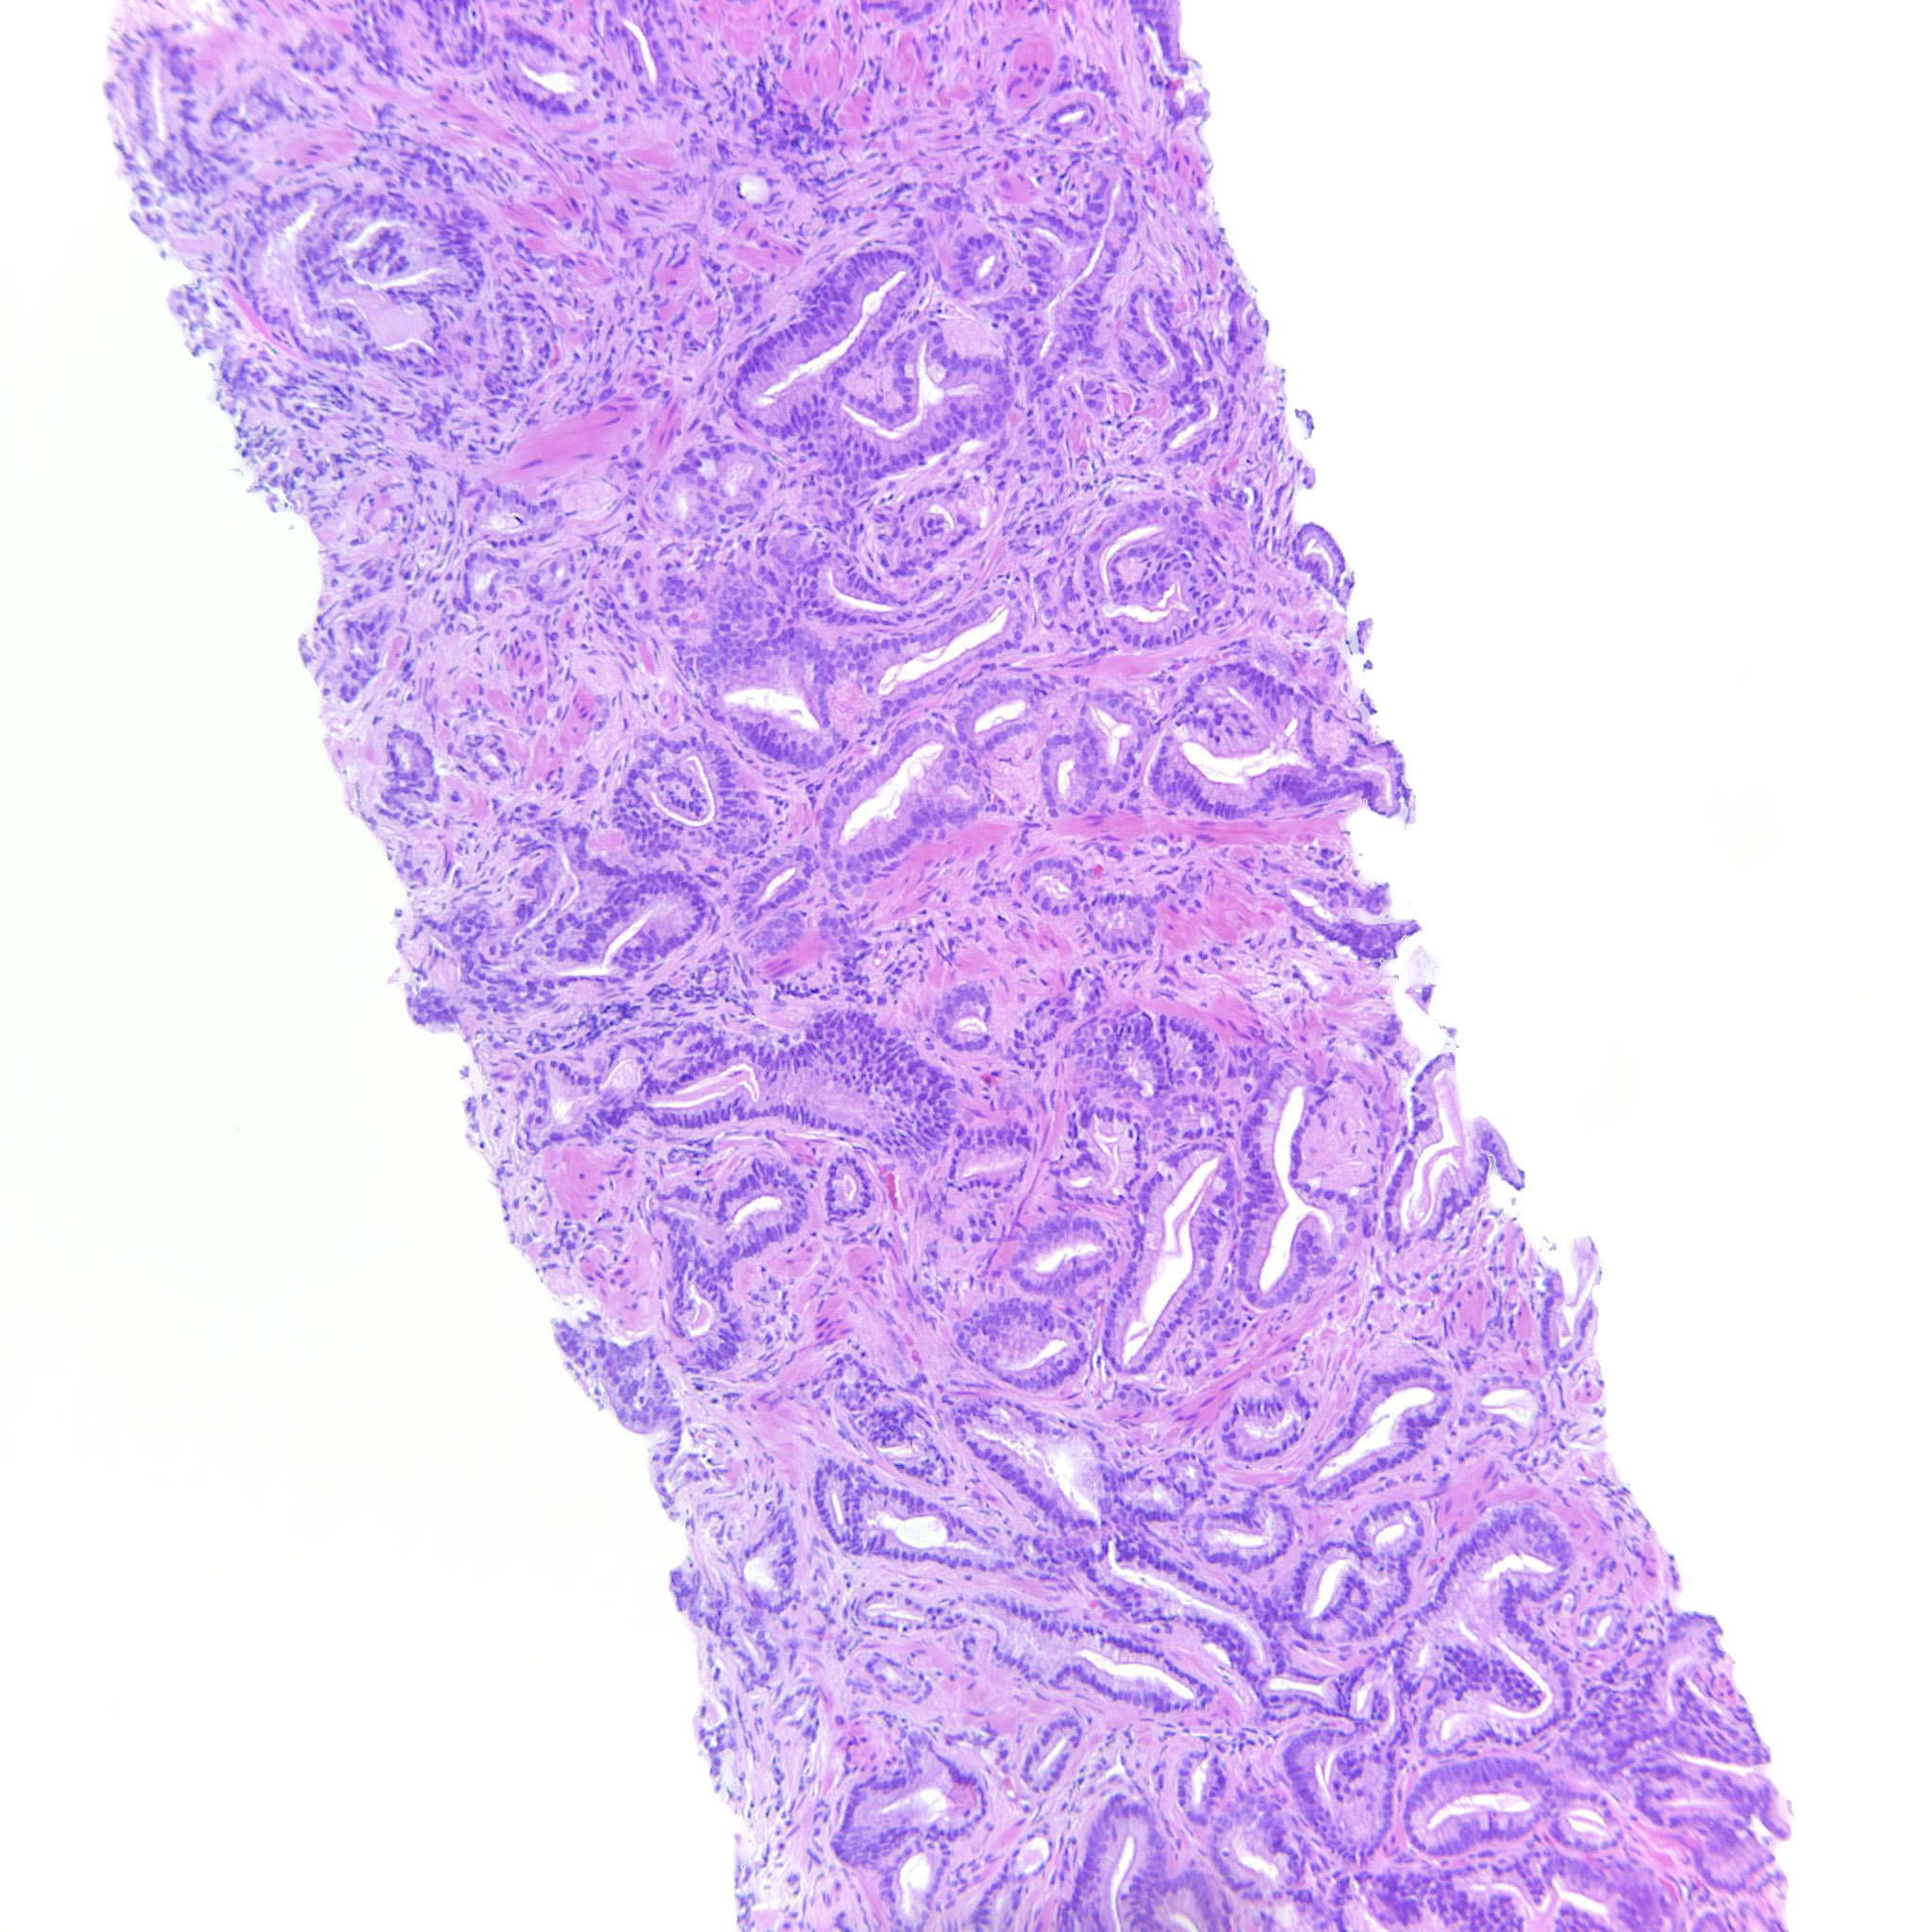

Prostate cancer grading

Case ID: 516